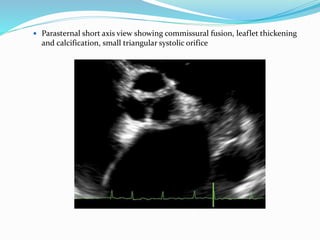

Rheumatic Aortic Stenosis

 Characterized by

 Commissural fusion

 Triangular systolic orifice

 thickening & calcification

 Accompanied by rheumatic

mitral valve changes.

 Parasternal short axis view showing commissural fusion, leaflet thickening

and calcification, small triangular systolic orifice